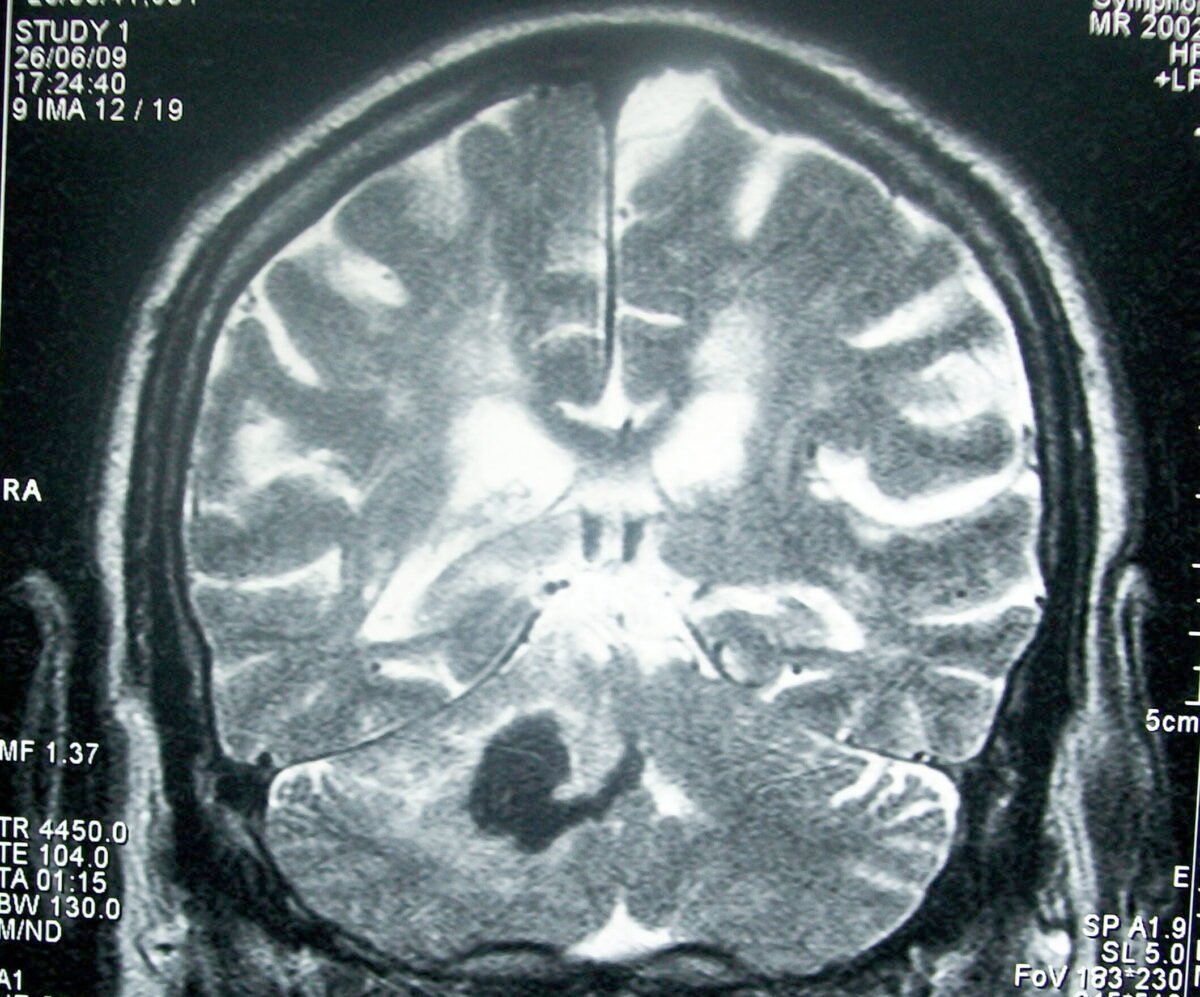

Día Mundial del Accidente Cerebrovascular

El Día Mundial del Accidente Cerebrovascular (ACV) se conmemora cada 29 de octubre y está dedicado a aumentar la conciencia pública sobre la prevención, el reconocimiento temprano, el tratamiento oportuno y la rehabilitación después del ACV. La fecha es el punto central de una campaña global impulsada por la World Stroke Organization (WSO) y socios … Leer más